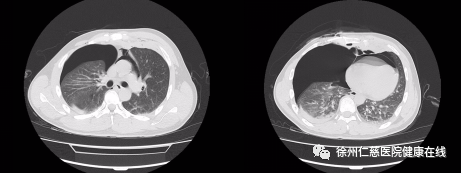

徐州仁慈医院急诊医生对胸部伤口进行紧急加压包扎,随后经 CT 检查发现李师傅出现了心包积气与气胸,情况十分危险,随即联络胸外科王保毅主任进行紧急手术。

入院 CT 显示患有心包积气与气胸